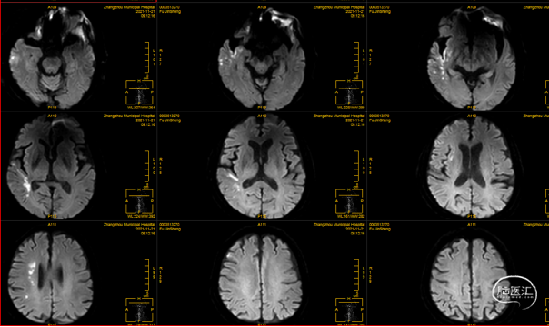

术后影像学检查

术后24小时CT:右侧侧脑室旁低密度

术后72小时DWI:右侧额颞叶、岛叶、侧脑室旁急性脑梗死。